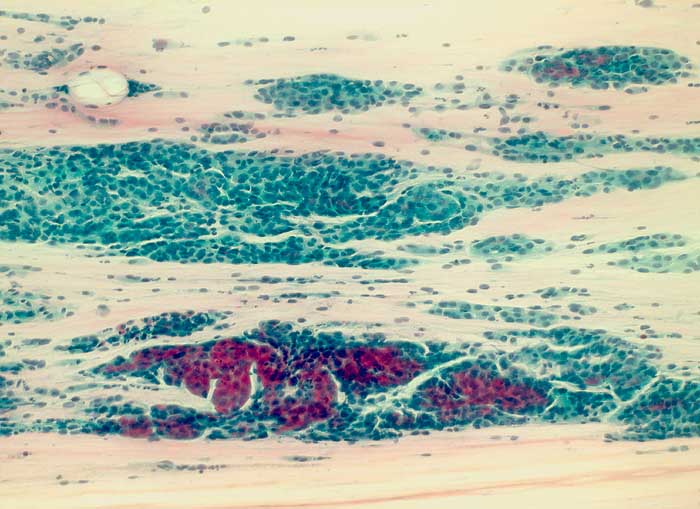

g/ Seröses Adenokarzinom des Endometrium

Seröses Adenokarzinom des Endometrium

Die Zellkerne der serösen Adenokarzinome sind in den meisten Fällen hochgradig atypisch. Das Zellbild gleicht entsprechend demjenigen eines wenig differenzierten endometrioiden Adenokarzinoms. Da das seröse Karzinom anders als das endometrioide Karzinom nicht Folge eines Hyperöstrogenismus ist, zeigen die meist postmenopausalen Patientinnen keinen hohen Aufbau des Vaginalepithels im PC-Abstrich.